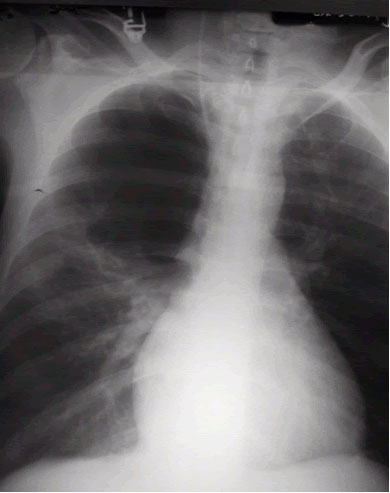

| Figure 1. Large right-upper lobe lucency |

The patient was afebrile and hemodynamically stable. However, pulse oximetry registered 70% as the patient was receiving 4 liters of oxygen by nasal canula. On physical examination, the patient had diminished breath sounds in the right-upper chest and diffuse expiratory wheezing. An arterial blood gas (ABG) in the ED revealed a pH 7.23, PaCO2 126 mm Hg, PaO2 37 mm Hg and SaO2 72%. An admission chest roentogram was obtained and revealed a large right-upper lobe lucency without evidence of pneumothorax (Figure 1). The patient was endotracheally intubated in the ED for respiratory distress, and a repeat ABG (pH 7.39, PaCO2 83 mm Hg, PaO2 160 mm Hg and SaO2 92%) on ventilator settings of tidal volume 500 ml, no positive end-expiratory pressure, respiratory rate of 20 breaths per minute and 50% FiO2 showed improvement. Following intubation, the patient was admitted to the MICU and aggressive pulmonary therapy was pursued. Intravenous steroids, frequent nebulizers and intravenous antibiotics were also administered. Chest computed tomography (CT) demonstrated a massive right apical bulla occupying nearly one-third of the right hemithorax along with several smaller bullae seen throughout the right and left lungs (Figure 2). The patient subsequently improved, and was able to be extubated on the morning of the second hospital day. A post-extubation ABG on 2 liters of oxygen by nasal canula was pH 7.36, PaCO2 85 mm Hg, PaO2 55 mm Hg and SaO2 85%. Pulmonary function tests (PFTs) revealed an FEV1 of 0.39 liters (9% of predicted) and a FVC of 0.8 liters (16% of predicted).